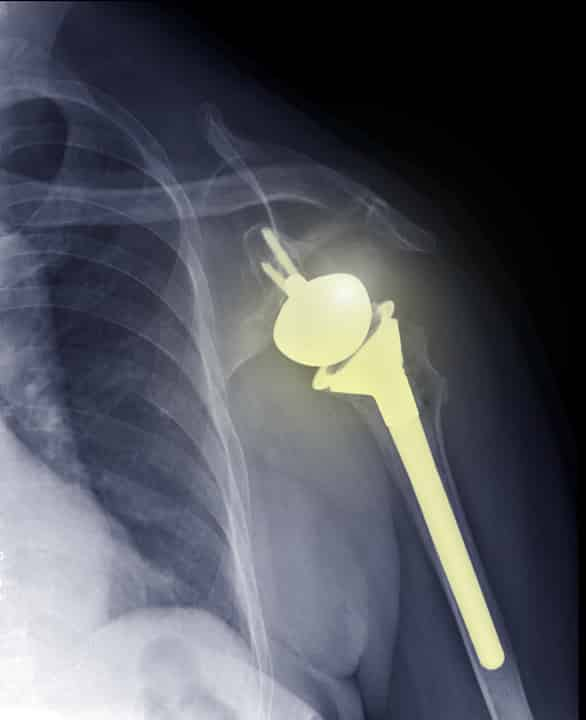

Mixed Reality Shoulder Surgery . Stryker announced completion of the first shoulder joint replacement surgeries using blueprint mixed reality (mr) guidance. Shoulder arthroplasty, or shoulder replacement surgery, is a complex procedure where damaged bone is replaced by metal and plastic implants. Stryker today announced that its blueprint mixed reality (mr) guidance system, which was cleared by fda in january 2023, has been used in its first shoulder arthroplasty surgeries. Lionel neyton, md, orthopaedic shoulder surgeon at centre orthopédique santy and hôpital privé jean mermoz in. Stryker has announced that the first shoulder arthroplasty surgeries using blueprint mixed reality (mr) guidance in europe have been successfully completed by professor julien berhouet, md, phd, chru tours hospital, france, and dr. Stryker announced that the first shoulder replacement surgeries using its blueprint mixed reality (mr) guidance were successfully. Stryker has announced that the first shoulder arthroplasty surgeries using blueprint ® mixed reality (mr) guidance have been successfully completed by dr. Joseph’s health care london, canada. The first mixed reality navigated shoulder replacement surgery in the united states took place in early 2024. Blueprint mr combines stryker’s software with the microsoft hololens 2 headset, allowing surgeons to track the position and orientation of surgical instrumentation in the physical environment.